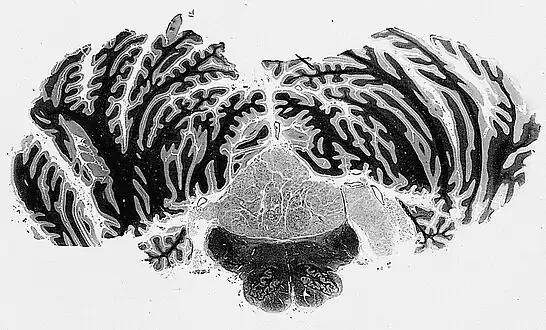

| Micrograph of a subependymoma showing the characteristic clustering of nuclei. H&E stain. | |

The diagnosis is based on tissue, e.g. a biopsy. Histologically subependymomas consistent of microcystic spaces and bland appearing cells without appreciable nuclear atypia or mitoses. The nuclei tend to form clusters.